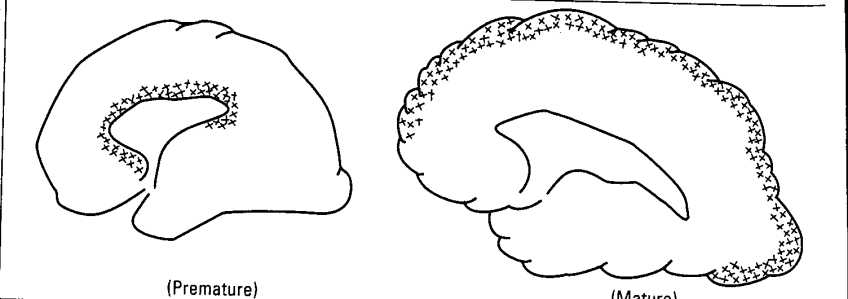

早产儿 足月儿

△ 脑室周围白质软化(早产儿PVL)

早产儿脑损伤(periventricular leukomalacia, PVL)